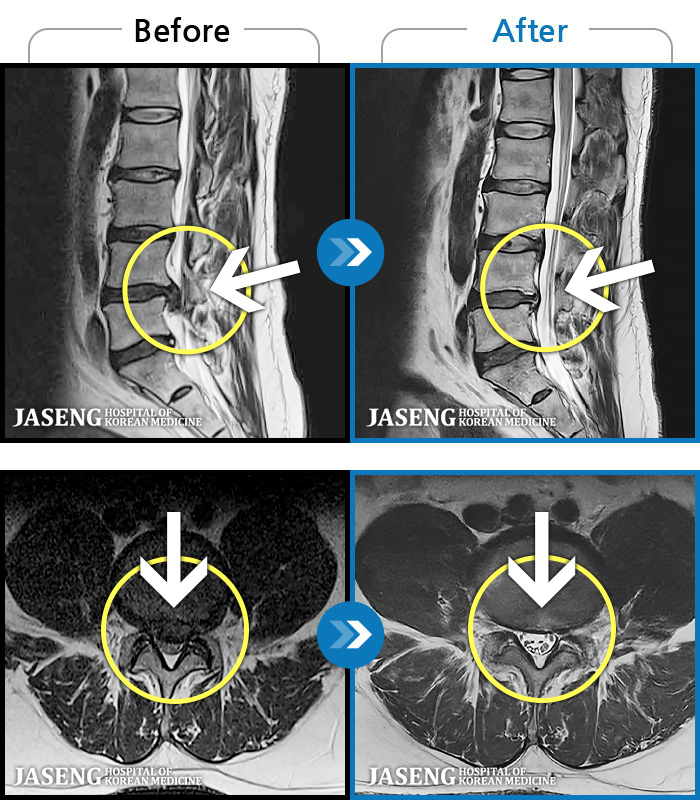

[뱸] 19.11.28~25.05.06